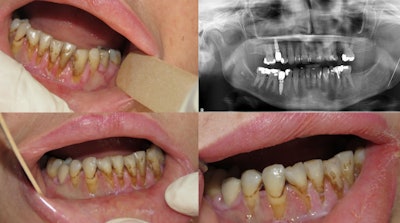

Diffuse gingival ulceration and recession. An orthopantogram showed multiple previous dental fillings and root canal treatment to control her pain. Image courtesy of Yazan Hassona.

At the visit, her vital signs were normal, and her dental exam was unremarkable. Imaging and vitality testing failed to show caries, tooth or root fractures, periodontal pockets, tooth surface loss, or any other dental condition. Therefore, persistent dentoalveolar pain was considered as a diagnosis. Additionally, the woman’s toothbrushing seemed to be atraumatic. She reported no history of dental trauma, and lab tests showed nothing remarkable.

A year later, the woman visited an emergency department at another hospital due to the same complaints. At this time, the woman had multiple missing teeth. They were extracted at different clinics to relieve her pain.